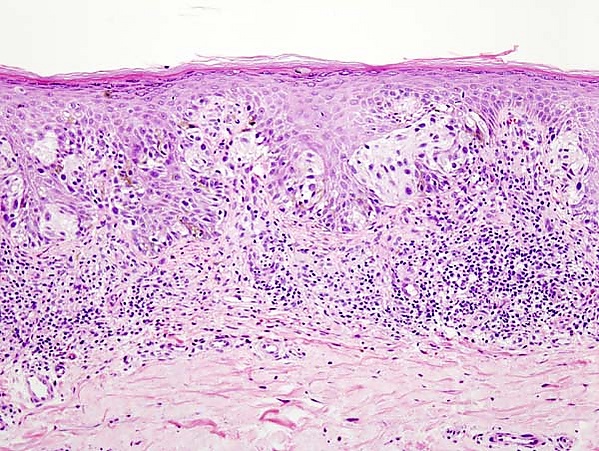

- Окончательный диагноз меланомы может быть установлен только после гистологического исследования, проведённого после тотального удаления невуса (опухоли) с достаточным захватом здоровых тканей. Предоперационная биопсия с помощью иглы или частичного удаления противопоказана, во избежание распространения меланомы. Определяется глубина прорастания (Clark, Breslow) и митотический индекс.

Стадии меланомы кожи

- Уровень I: все опухолевые клетки находятся в эпидермисе, до базальной мембраны

- Уровень II: клетки опухоли инфильтрируют сосочковый слой дермы

- Уровень III: опухоль достигает границы между сосочковым и сетчатым слоями дермы

- Уровень IV: опухолевые клетки обнаруживаются в сетчатом слое дермы

- Уровень V: опухоль прорастает в жировую клетчатку